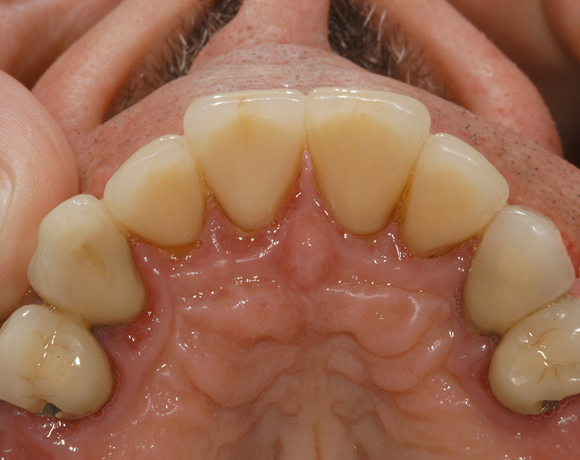

Üblicherweise werden Teleskopkronen aus Metalllegierungen hergestellt. Der Nachteil dieser Prothesenkonstruktion für den Patienten ist, wenn er seine Prothese aus dem Mund nimmt sieht man nur noch gold- oder silberfarbene Zahnstümpfe. Mit den Innenteleskopen aus e.max Press sieht man zahnfarbene Stümpfe, die unserem ästhetisches Verständnis nicht gleich ins Auge stechen.

Im vorliegenden Patientenfall musste eine komplette Neukonstruktion der Oberkieferversorgung vorgenommen werden, da auf Grund parodontaler Probleme die Seitenzahnbrücken 15 – 17 und 25 – 27 nicht mehr zu halten waren. Die verbliebenen acht Frontzähne bzw. Prämolaren waren auch parodontal vorgeschädigt und es war ungewiss wie lange sie einzelne noch halten lassen. Um nicht bei jedem Verlust eines der Restzähne eine Neukonstruktion zu brauchen, hat man sich für eine Teleskopprothese entschieden. Für den Patienten war es allerdings nicht vorstellbar goldfarbene Primärteile im Mund zu haben, so wurde der Versuch unternommen diese aus e.max Press und Galvano Sekundärteilen herzustellen.